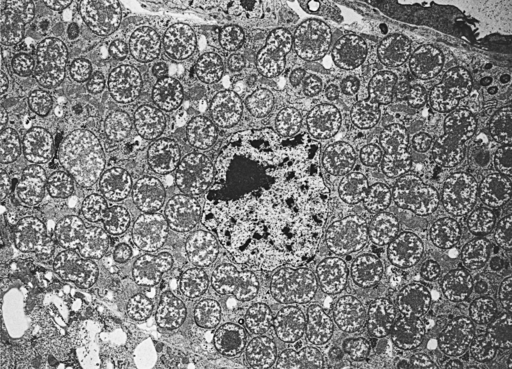

Bakterie Yersinia pseudotuberculosis (rod Yersinia, čeleď Enterobacteriaceae) je původcem pseudotuberkulózy – bakteriálního onemocnění savců i ptáků, které je charakterizováno akutní septikémií a tvorbou sýrovitých uzlů (kaseózních nodulů) ve viscerálních orgánech, připomínajících tuberkulózní granulomy. Wikipedia

Yersinia pseudotuberculosis je G−, pleomorfní tyčinka. Při nižších teplotách je schopna pohybu. Tento organismus byl popsán v roce 1889 jako choroba guinejských vepřů. Avšak Yersinia pseudotuberculosis se ukázala jako předek Yersinia pestis, která byla příčinou pandemického moru během let 541−767.